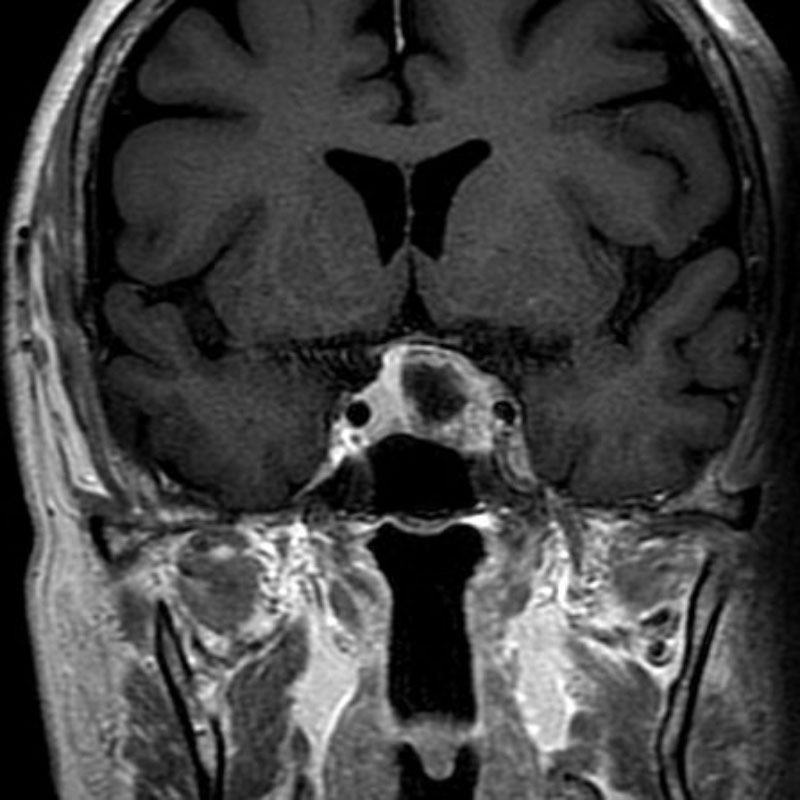

589

'24年11月

70代

第三脳室髄膜腫

頭蓋内腫瘍摘出術

No.’24_91 手術前1

No.’24_91 手術前2

No.’24_91 摘出 前

No.’24_91  摘出 中

No.’24_91 摘出 後